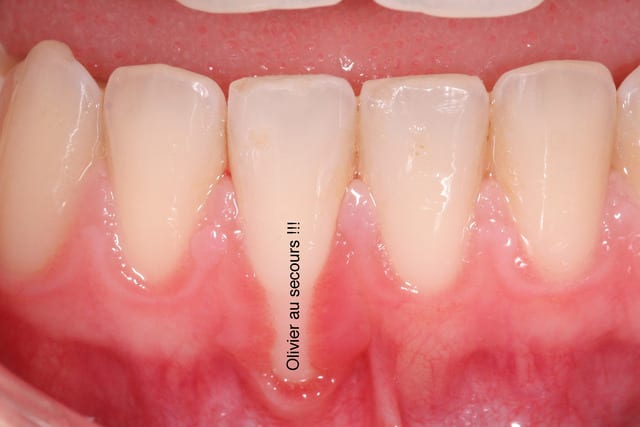

pas mécontent du modelage en vestibulaire et de la "papille" interimplantaire. on verra à la maturation ce que ça devient.

Mucco ohwxyi - Eugenol

Joli

céramik tu es mon jiminy criquet je va m'appliquer mieux